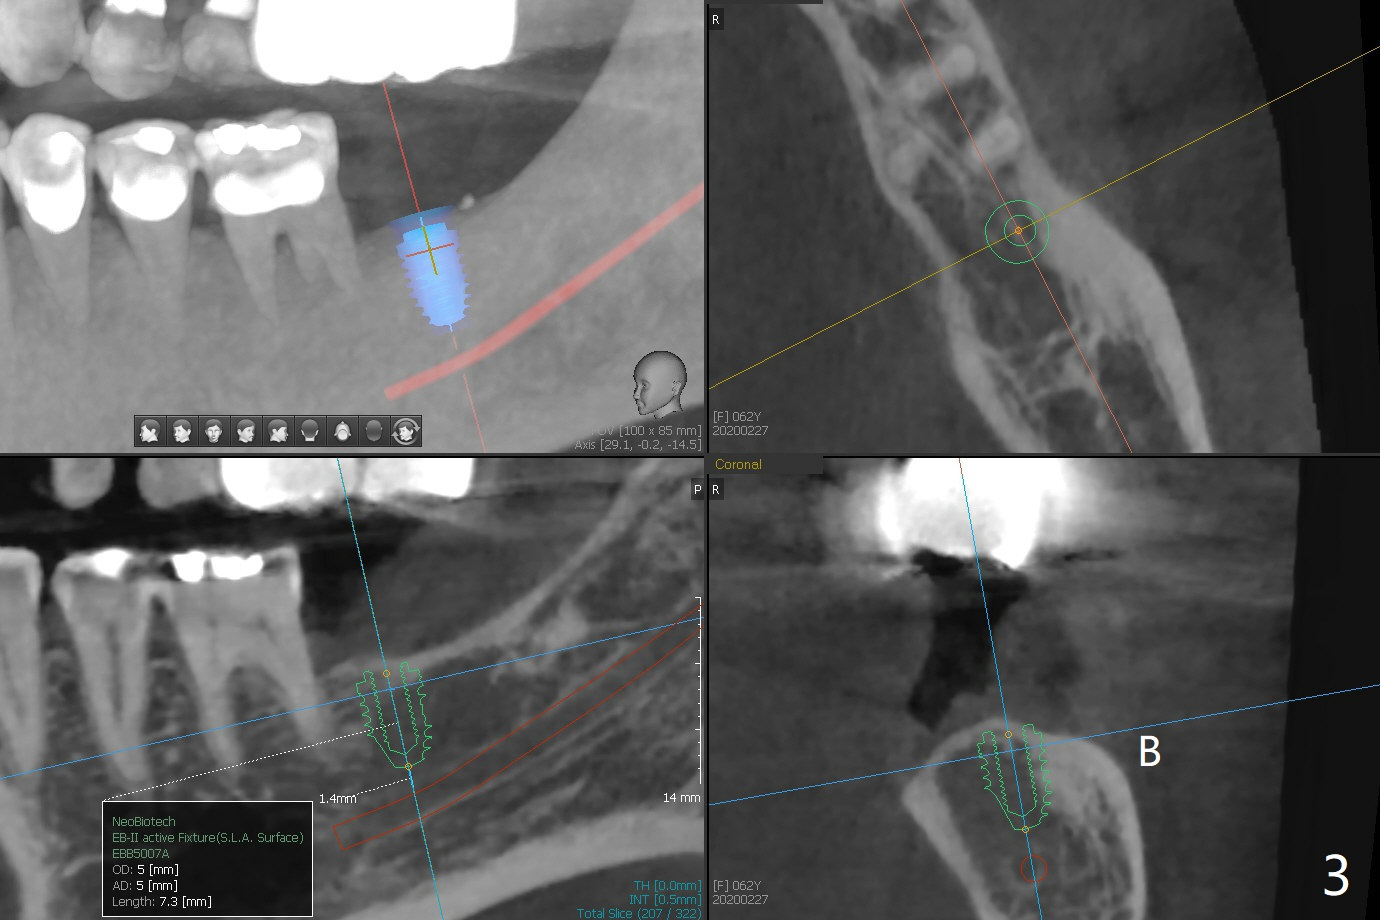

A 62-year-old woman returns for #18 implant with guide 3 months post #14 crown cemen-tation (Fig.1). The implant at #14 was placed free hand after guided osteo-tomy. It appears that its buccal plate is thin (Fig.2). Full guided surgery seems to be nece-ssary.